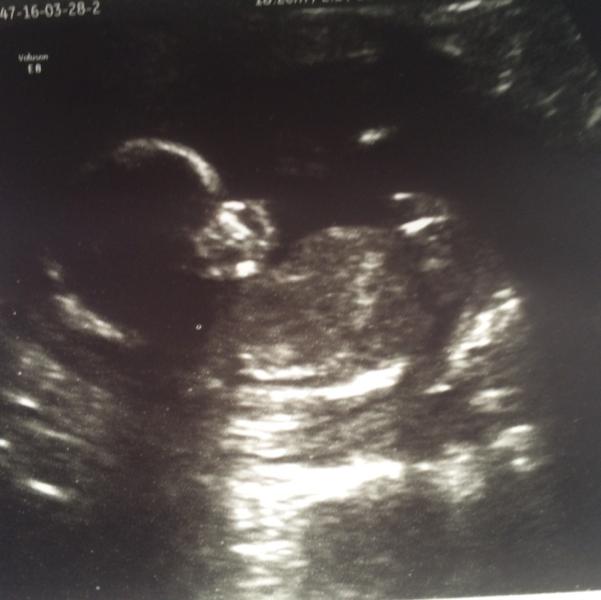

Сходили к Романовской. Мальчик 👶 муж под впечатлением 🙈

@guma6, спасибо ) В жк3 на Ульяновском, врач Бехлер. Меня она устраивает, достаточно внимательно ведёт ☺️ а к Романовской пошла чтобы мужу показать что не просто так живот растёт, что там тааакие танцы 😂 ну и чтобы в командировку уже со спокойной душой ехать, что все ттт хорошо ☺️